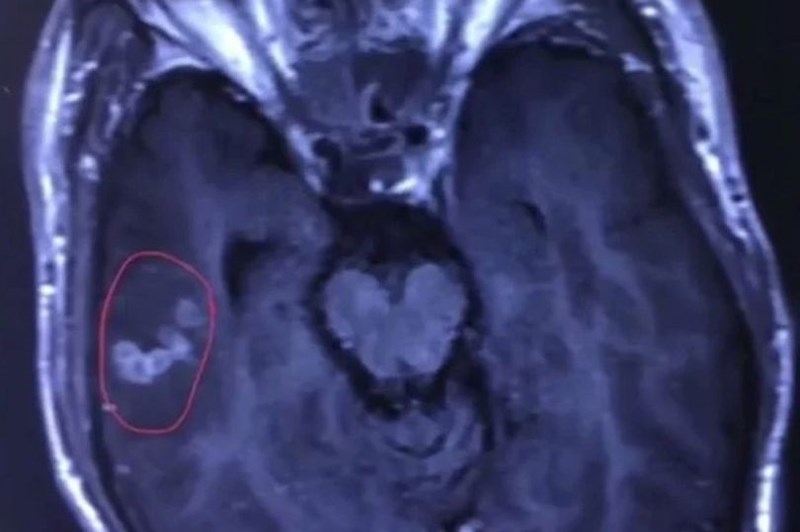

Một thanh niên họ Liu, 26 tuổi sống ở Trung Quốc bỗng dưng mắc chứng động kinh dữ dội. Sau khi được đưa vào bệnh viện First Affiliated của Đại học Nam Xương kiểm tra, các bác sĩ sững sờ phát hiện ra có một con sán dây vẫn đang sống trong não bệnh nhân, Bưu điện Hoa Nam buổi sáng đưa tin.

Phim chụp X- Quang cho thấy con sán bên trong não bệnh nhân. Ảnh: SCMP

Bác sĩ Wang Chunliang, người thực hiện ca mổ gắp con sán ra khỏi não nạn nhân cho biết, con sán dài khoảng 10 cm và vẫn còn ngọ nguậy. Có thể bệnh nhân đã ăn đồ tươi sống bị nhiễm kí sinh trùng sán. Sau khi xâm nhập cơ thể, kí sinh trùng đã theo máu, đến não và sinh trưởng tại đó.